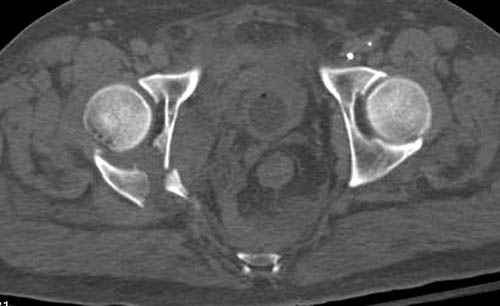

Имя     : 1Proximal hum+acetabulum CT.jpg

Тип     : image/jpeg

Размер  : 20757 байтов

Описание: отсутствует

Url     : http://weborto.net:8080/pipermail/ortho/attachments/20071130/37ea88e5/attachment-0011.jpg